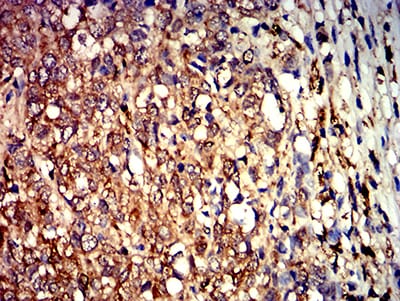

Immunohistochemical analysis of paraffin-embedded human breast cancer tissues using ALDOA mouse mAb with DAB staining.